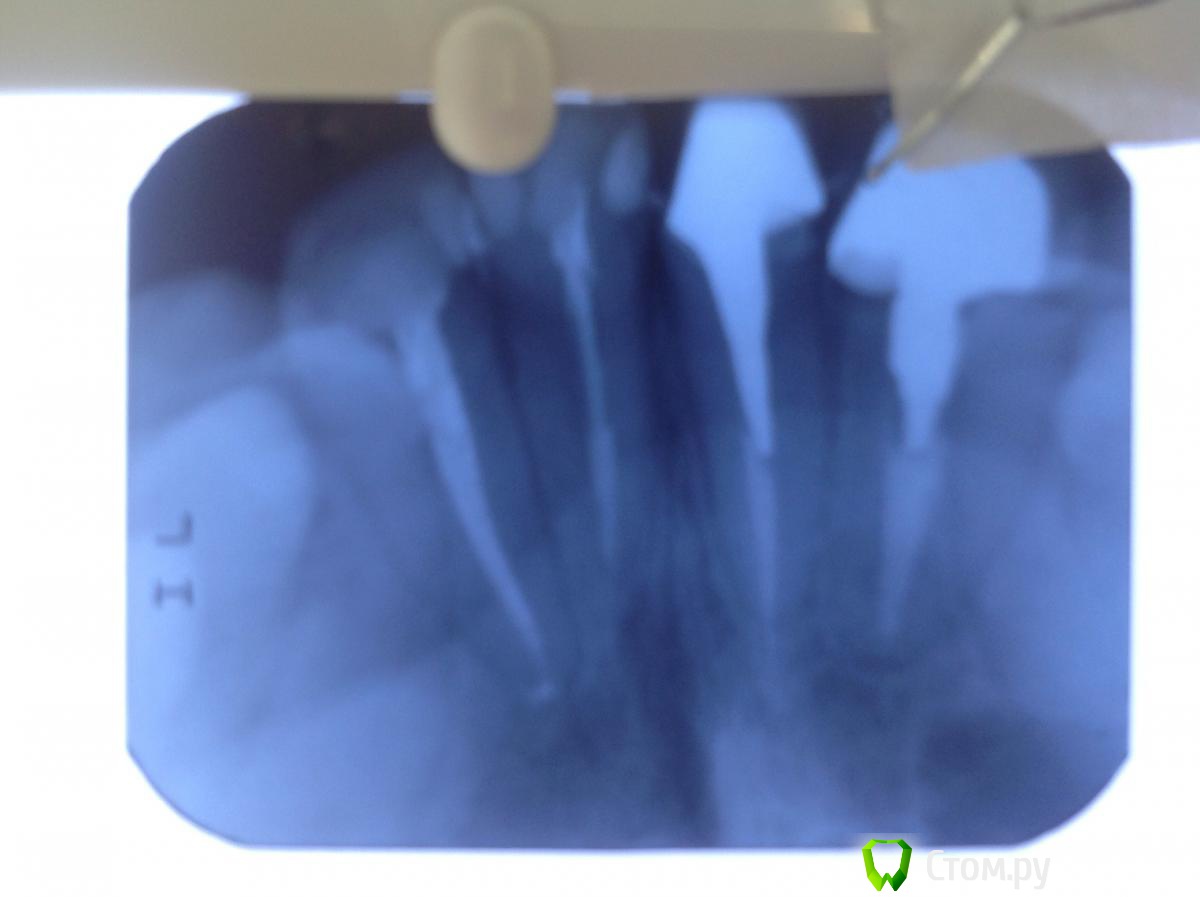

StomDoc Опубликовано 26 ноября, 2013 Поделиться Опубликовано 26 ноября, 2013 Пациентка обратилась с жалобой на скол 11 зуба, доктор поставил метал вкладку но уступа практически нет так же как и на 12 где м/к коронка и вкладка планирую поднять зениты на 11 и 12 зубах тем самым получить хоть какой то минимальный феррул. Какое ваше мнение? И если ставить циркон на передние зубы нужно можно ли их поставить на метал вкладку?? Ссылка на комментарий